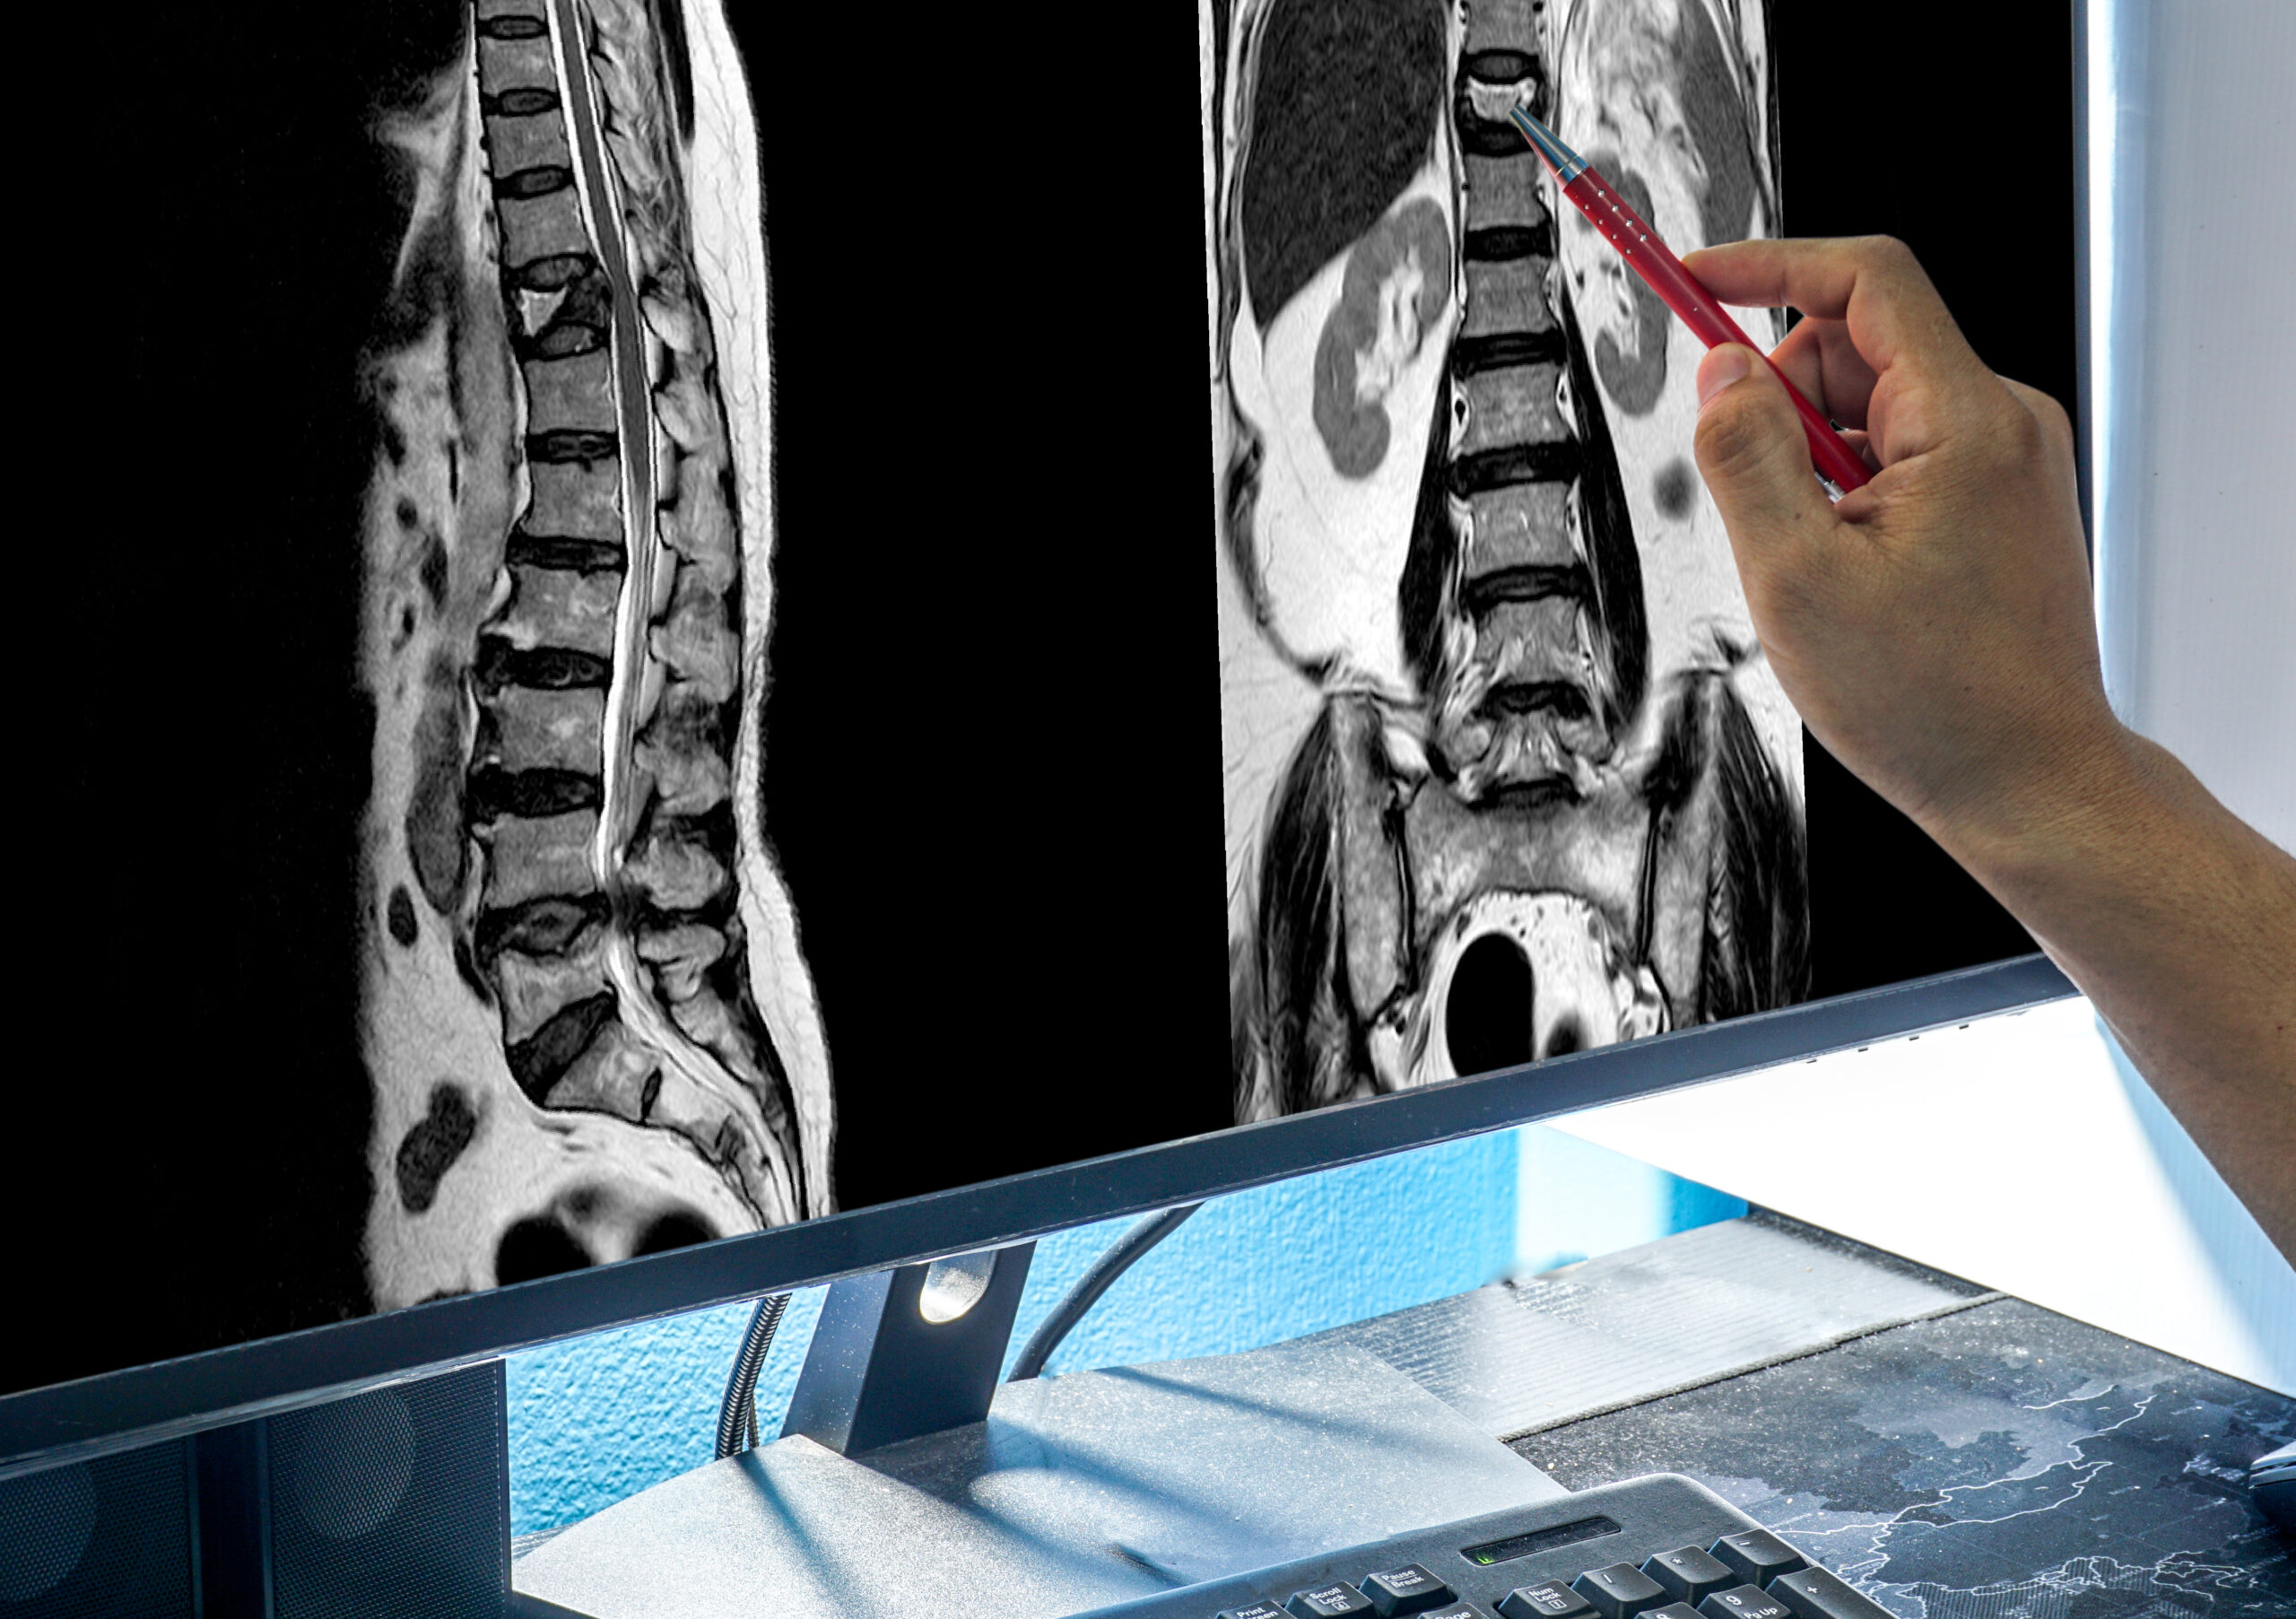

Spinal stenosis is a condition that affects millions of people, especially those above the age of 50. Characterized by the narrowing of the spinal canal, stenosis in Rajajinagar patients commonly experience symptoms such as lower back pain, leg cramps, numbness, tingling, and in severe cases, difficulty walking or standing for long periods.

Spinal stenosis occurs when the spaces within the spine become narrowed, putting pressure on the spinal cord or nerves. This can happen due to:

Most patients develop lumbar (lower back) or cervical (neck) stenosis, often resulting in pain, numbness, or muscle weakness, especially in the legs and arms.

- You have been diagnosed with lumbar or cervical spinal stenosis through MRI/CT scan